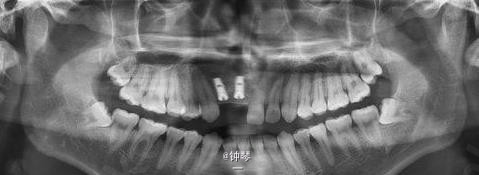

前牙种植+钛网应用

患者,女,30岁,右上1,2缺失要求种植。平素体质一般,否认高血压、糖尿病及心脏病史,否认肝炎、结核病史,无药物、食物过敏史,无外伤、手术及输血史。